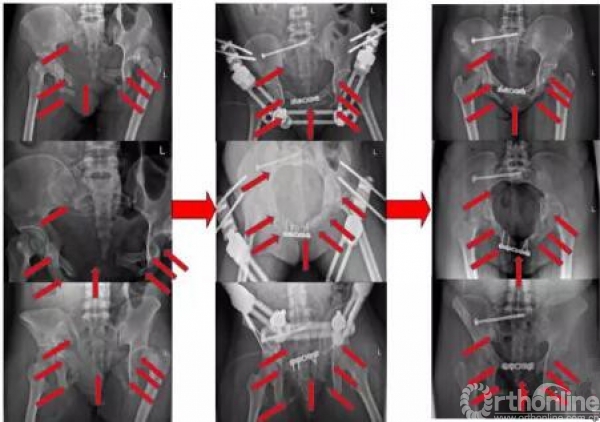

术后复查影像(2017.09.28、2017.10.05)

术后x线(2017.09.17)

骨盆正位、骨盆入口位、骨盆出口位

患者2 随访(C2型):骶骨螺钉+外固定架+小切口钢板

患者3 随访(C2型):骶骨螺钉+耻骨支螺钉+小切口钢板

患者4 随访(B2型):经皮骶骨螺钉+INFIX前环内固定架

患者5 随访(骨盆LC-2损伤+髋臼):经皮LC-2螺钉+前柱螺钉

患者6 随访(U型骨折脱位):经皮骶髂贯穿螺钉

患者7 随访(C2型):经皮骶骨螺钉+前柱螺钉+外固定架